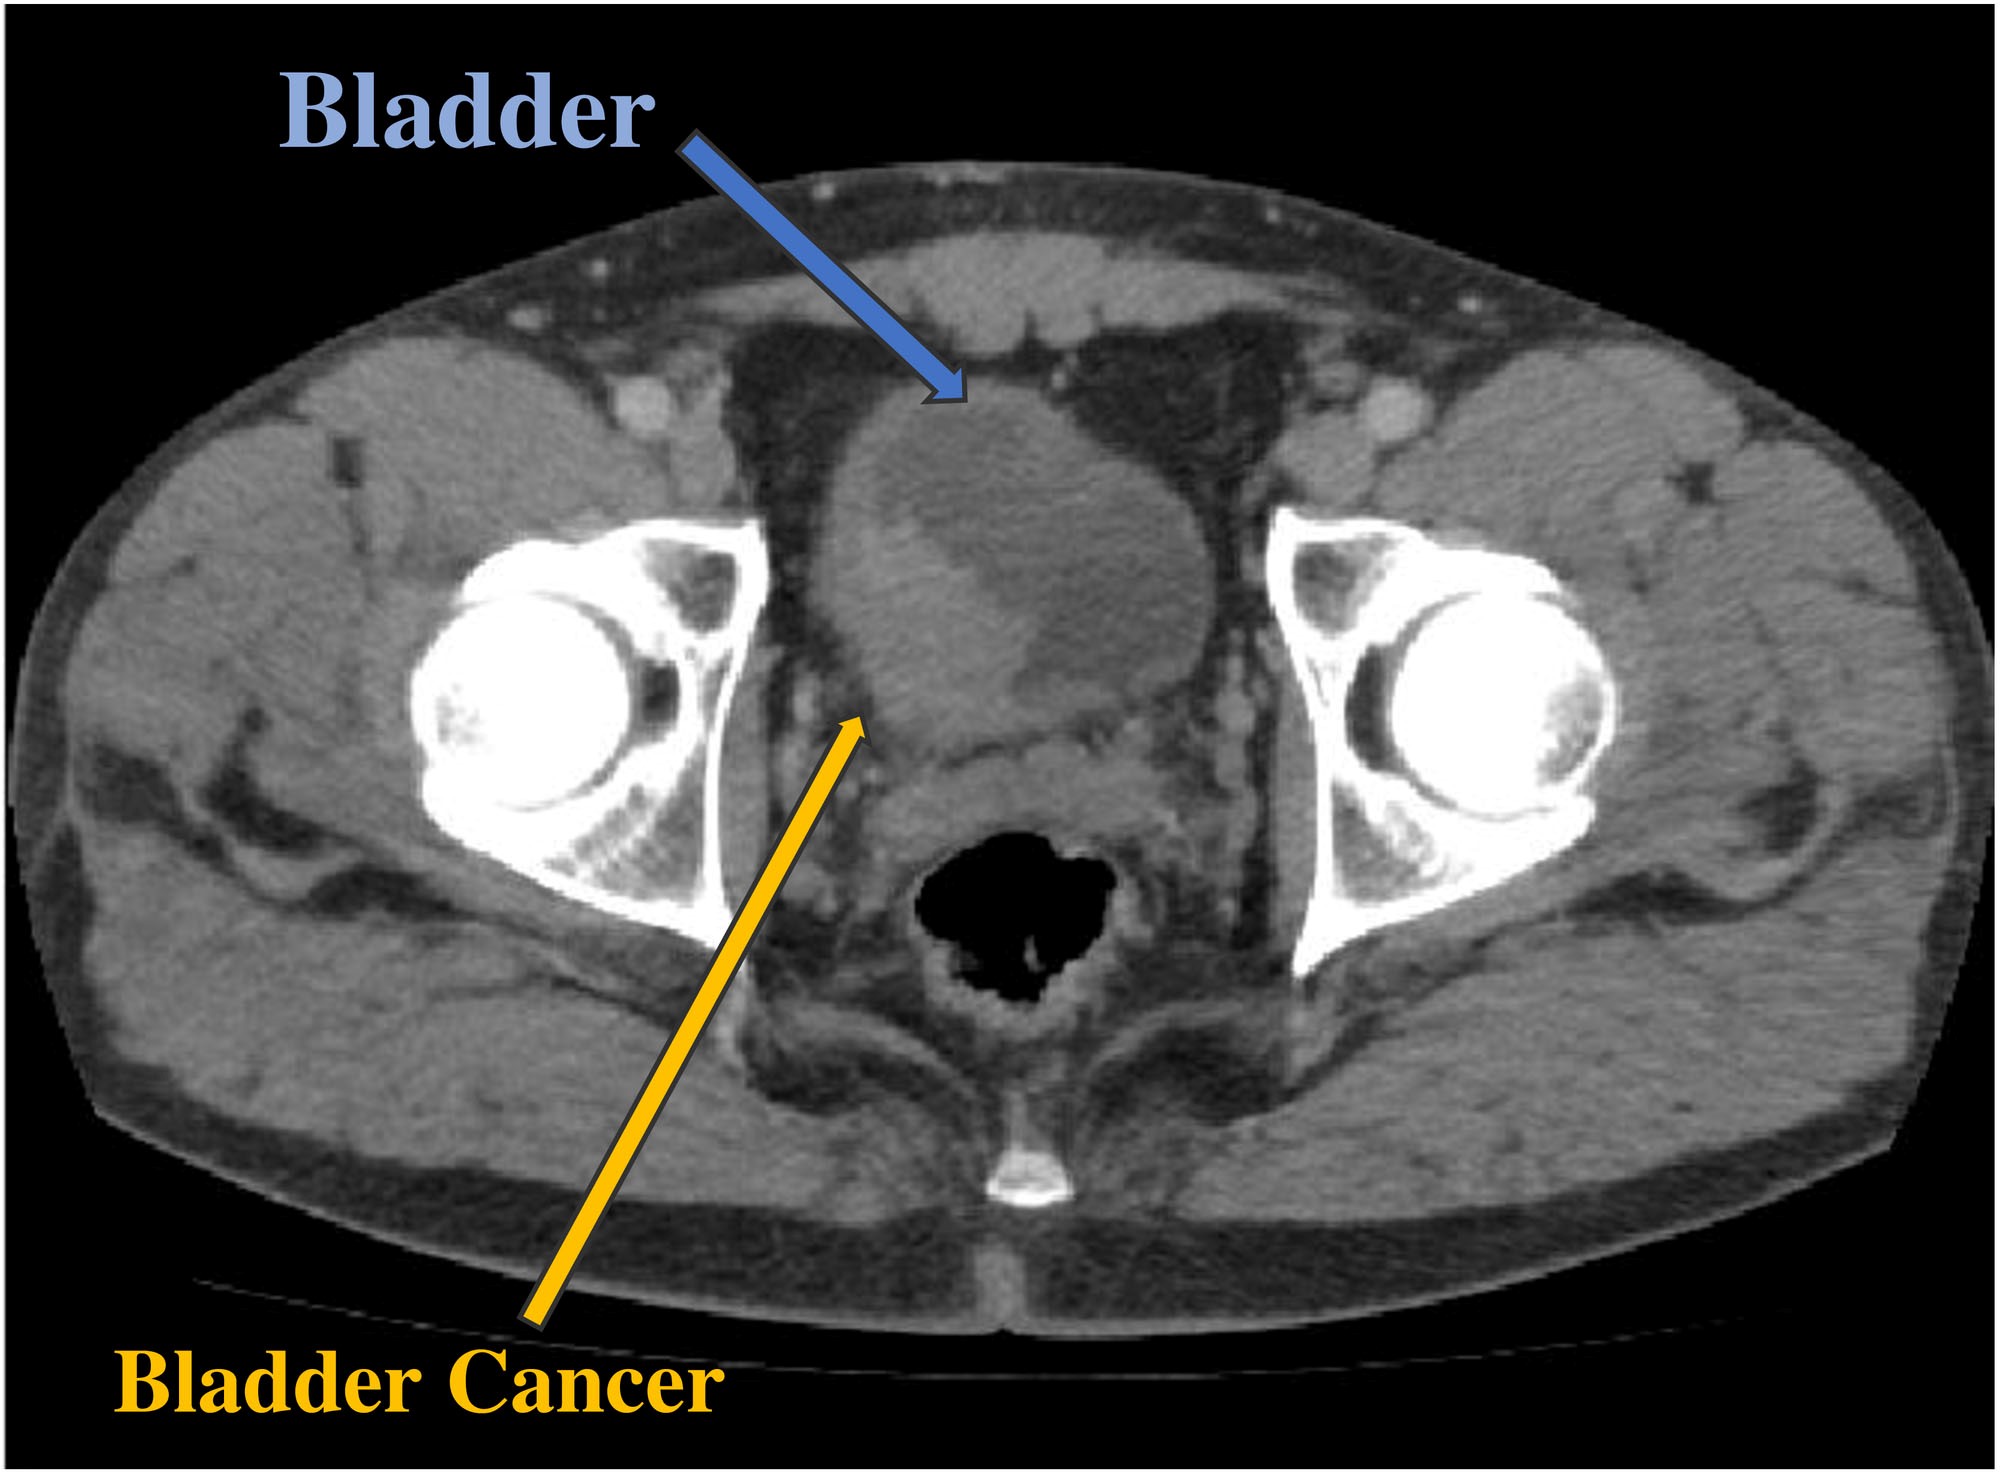

Bladder Cancer Chin Chong Min Urology Robotic Surgery Centre

Bladder Cancer Pathophysiology Wikidoc